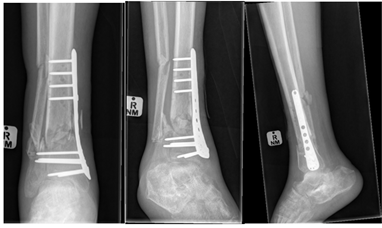

There were 61 males (61%) and 39 females (39%). The median age of the participants was 36 (47-27) years, ranging from 18 to 77 years. A total of 80 patients (80.0%) were treated with intramedullary nailing, 20 (20.0%) treated with plating. In the plated group, 15 were treated with anterolateral plates (75%) and five treated with medial plates (25%). Five of the plate cases were more distal and comminuted and not amenable to intramedullary nailing. The immediate post-operative AP X-Ray views showed that 73 participants had an acceptable alignment (73%) and 27 had malalignment (27%) (Figure 3 & 4). Lateral view showed that 98 participants had acceptable alignment, with unacceptable alignment in only two patients.

Figure 3 Malunion post IMN.

Figure 4 Malunion post IMN.